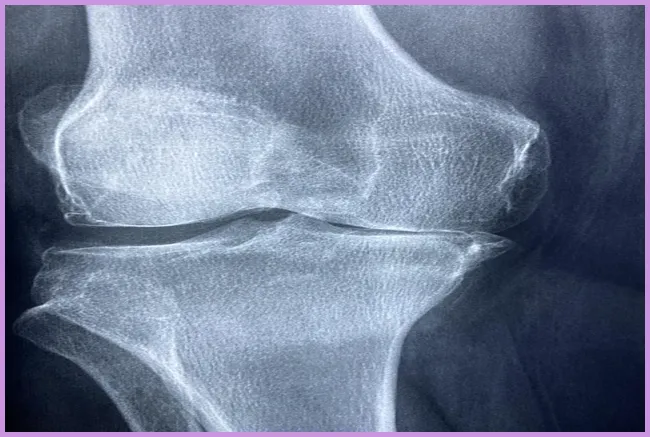

퇴행성 관절염의 원인은 무엇인가요?

퇴행성 관절염의 주요 원인으로는 노화, 비만, 유전적 요인, 및 관절의 과도한 사용이 있습니다. 이러한 요인들은 관절 연골의 퇴화를 초래해 통증과 기능 저하를 일으킵니다.

퇴행성 관절염의 원인과 증상

퇴행성 관절염은 주로 노화와 관련이 깊습니다. 나이가 들면서 관절의 유연성이 떨어지고, 연골이 줄어들어 통증을 느끼게 됩니다. 또한 비만, 과도한 운동, 유전적 요인 등이 퇴행성 관절염을 악화시킬 수 있습니다. 주요 증상으로는 관절의 경직, 통증, 불균형 등이 있습니다. 이런 증상을 경험할 때면 일상적인 활동도 어렵게 느껴지곤 하지요.